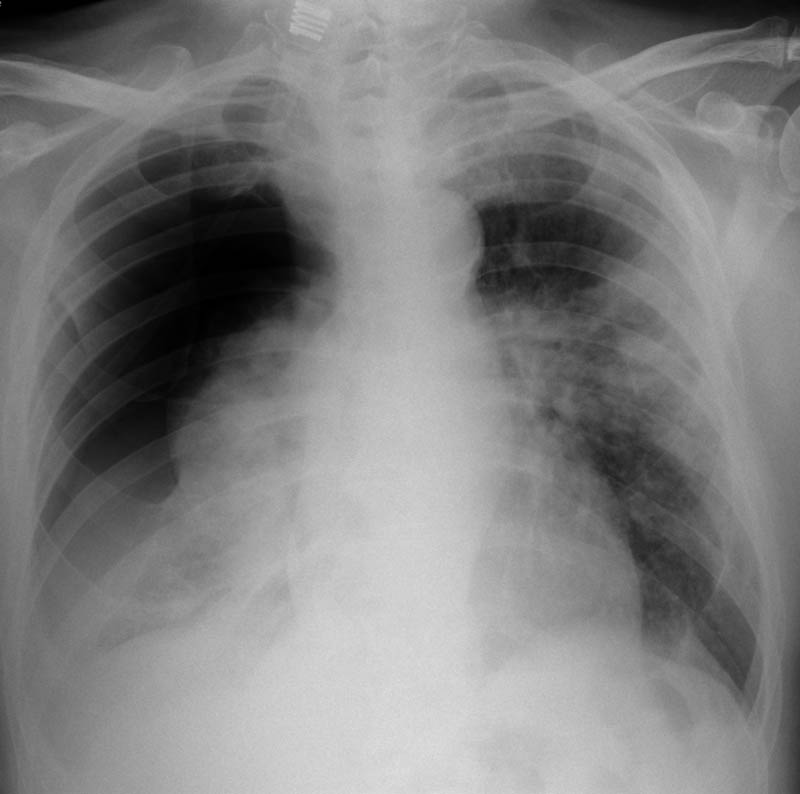

MO Distres respiratorio del adulto por trauma.